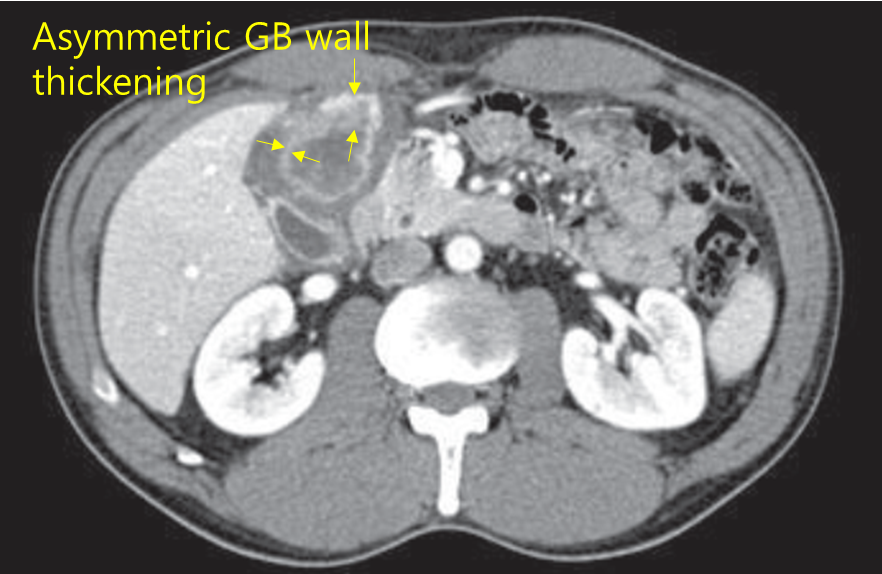

60세 남자가 최근 2개월 전부터 눈이 노랗게 되는 것 같다며 병원에 왔다. 몸을 가려워하지는 않는다. 10일 전 받은 식도위내시경 검사에서 특이 소견은 없다. 평소 건강하여 건강에는 관심이 없었다고 한다. 특이 과거력은 없다. 혈압 130/65 mmHg, 맥박 68회/분, 호흡 16회/분, 체온 36.8℃이다. 공막에 황달이 있지만 결막은 창백하지 않다. 복부진찰에서 뚜렷한 압통과 반동압통은 없고 만져지는 덩이도 없다. 혈액검사 결과는 다음과 같다. 복부 컴퓨터단층 촬영 사진이다. 진단은?

Img | CT: GB cancer |

황달을 주소로 내원한 환자로, 신체진찰에서 다른 특이소견은 확인되지 않고, 혈액검사에서 총빌리루빈과 ALP의 상승이 있고 CA19-9가 크게 상승해 있다. CT 사진에서 담낭 벽이 불규칙하게 비후되어 있는 악성 소견이 확인되므로, 담낭암으로 진단할 수 있다.

• 황색육아종성 담낭염은 만성 담낭염의 일종으로, colic pain, 발열, 황달 등 담낭염이나 담낭암과 비슷한 임상양상을 보인다. 영상소견 상에서 담낭벽의 비후를 나타내며 심한 경우 주변 조직을 침범하기도 하여 담낭암과 감별이 어려운 질환이다. 그러나 비교적 드문 질환이기도 하고, 담낭벽의 diffuse하기보다는 국소적인 비후 소견, CA19-9의 증가 등으로부터 담낭암의 가능성이 더 높다고 하겠다.